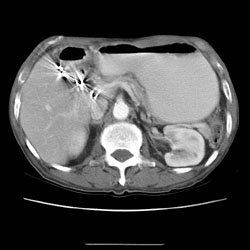

RADIOLOGY: AORTA: Case# 34023: ABDOMINAL AORTIC ANEURYSM. 83 year old male with weight loss. Very unusual configuration of abdominal aortic aneurysm.